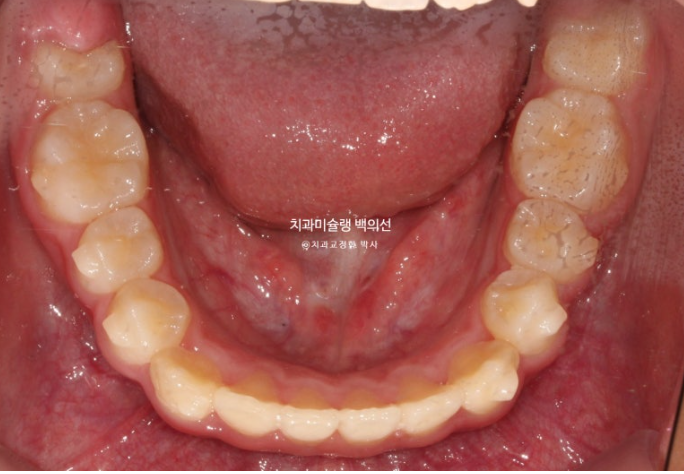

교합과 아래배열은 완벽하게 유지되고 있습니다.

25년 5월부터 25년 7월까지 앞니 배열 개선을 위해 추가장치를 짧게 낀 후 치료를 마무리 하였습니다.

25.07

중심선은 잘 맞으며

어금니 교합은 물샐틈 없는 1급 교합관계를 보입니다.